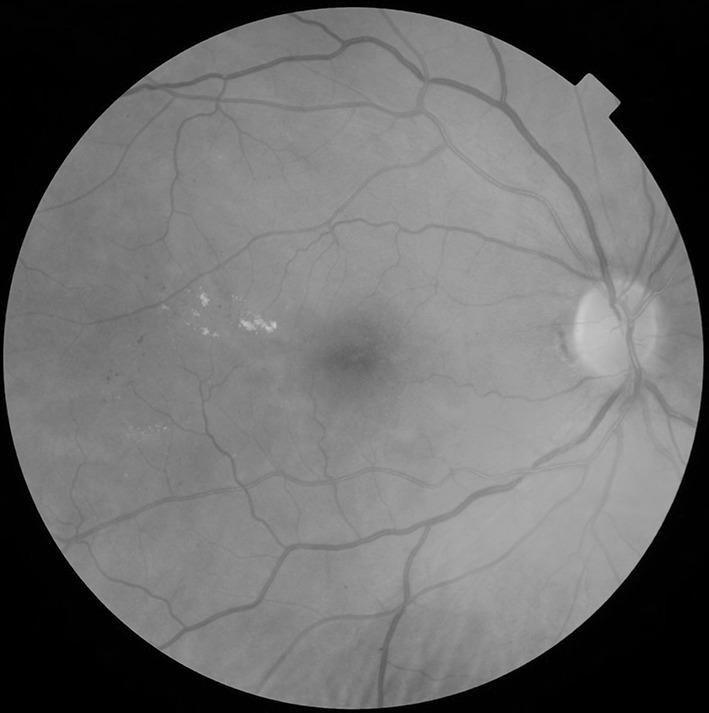

The aim of the English NHS Diabetic Eye Screening Programme is to reduce the risk of sight loss amongst people with diabetes by the prompt identification and effective treatment if necessary of sight-threatening diabetic retinopathy, at the appropriate stage during the disease process. In order to achieve the delivery of evidence-based, population-based screening programmes, it was recognised that certain key components were required. It is necessary to identify the eligible population in order to deliver the programme to the maximum number of people with diabetes. The programme is delivered and supported by suitably trained, competent, and qualified, clinical and non-clinical staff who participate in recognised ongoing Continuous Professional Development and Quality Assurance schemes. There is an appropriate referral route for those with screen-positive disease for ophthalmology treatment and for assessment of the retinal status in those with poor-quality images. Appropriate assessment of control of their diabetes is also important in those who are screen positive. Audit and internal and external quality assurance schemes are embedded in the service. In England, two-field mydriatic digital photographic screening is offered annually to all people with diabetes aged 12 years and over. The programme commenced in 2003 and reached population coverage across the whole of England by 2008. Increasing uptake has been achieved and the current annual uptake of the programme in 2015-16 is 82.8% when 2.59 million people with diabetes were offered screening and 2.14 million were screened. The benefit of the programme is that, in England, diabetic retinopathy/maculopathy is no longer the leading cause of certifiable blindness in the working age group.

英国国民保健制度糖尿病眼部筛查计划的目标是,在疾病进程的适当阶段,通过及时识别并在必要时对有视力威胁的糖尿病视网膜病变进行有效治疗,降低糖尿病患者失明的风险。为了实施基于证据、面向全体人群的筛查计划,人们认识到需要某些关键要素。为了将该计划覆盖到尽可能多的糖尿病患者,有必要确定符合条件的人群。该计划由经过适当培训、有能力且具备资质的临床和非临床工作人员实施并提供支持,这些人员参与公认的持续专业发展和质量保证计划。对于筛查结果呈阳性的患者,有适当的转诊途径以便其接受眼科治疗,对于图像质量不佳的患者,也有相应途径对其视网膜状况进行评估。对筛查结果呈阳性的患者而言,对其糖尿病控制情况进行适当评估也很重要。审核以及内部和外部质量保证计划已融入该服务之中。在英格兰,每年为所有12岁及以上的糖尿病患者提供双视野散瞳数码摄影筛查。该计划于2003年启动,到2008年已覆盖全英格兰所有人群。筛查参与率不断提高,在2015 - 16年度,该计划的当前年度参与率为82.8%,当时有259万糖尿病患者获得了筛查机会,其中214万人接受了筛查。该计划的益处在于,在英格兰,糖尿病视网膜病变/黄斑病变不再是劳动年龄组可认证失明的主要原因。